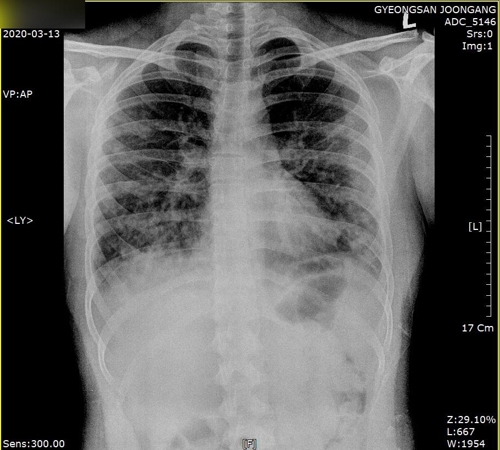

폐렴 증상이 있는 경우 X-ray 뿐만 아니라 배양검사를 통해 상태를 진단할 수 있으며, 필요시 소변검사, 혈청검사, 혈액검사, CT 등을 추가로 시행합니다. 진단받은 모든 환자에게 입원을 권유할 수는 없으나, 연령이 젊거나 그 반대이거나, 기저질환이 있거나, 연령이 높거나, 호흡곤란, 임산부 등의 경우 상태가 급격히 호전된다고 판단되는 경우 치료 및 위험 치료가 필요하며 입원 치료가 수행됩니다.